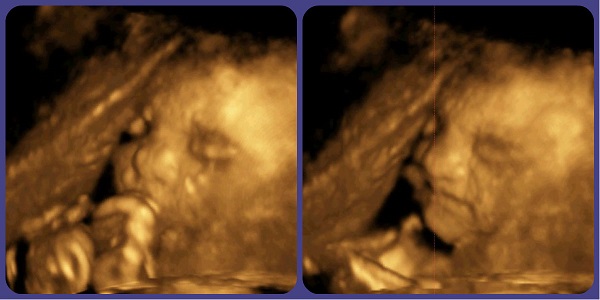

Ну и пара фотографий нашего маленького мужчины ^.^

Сосем палец и улыбаемся)